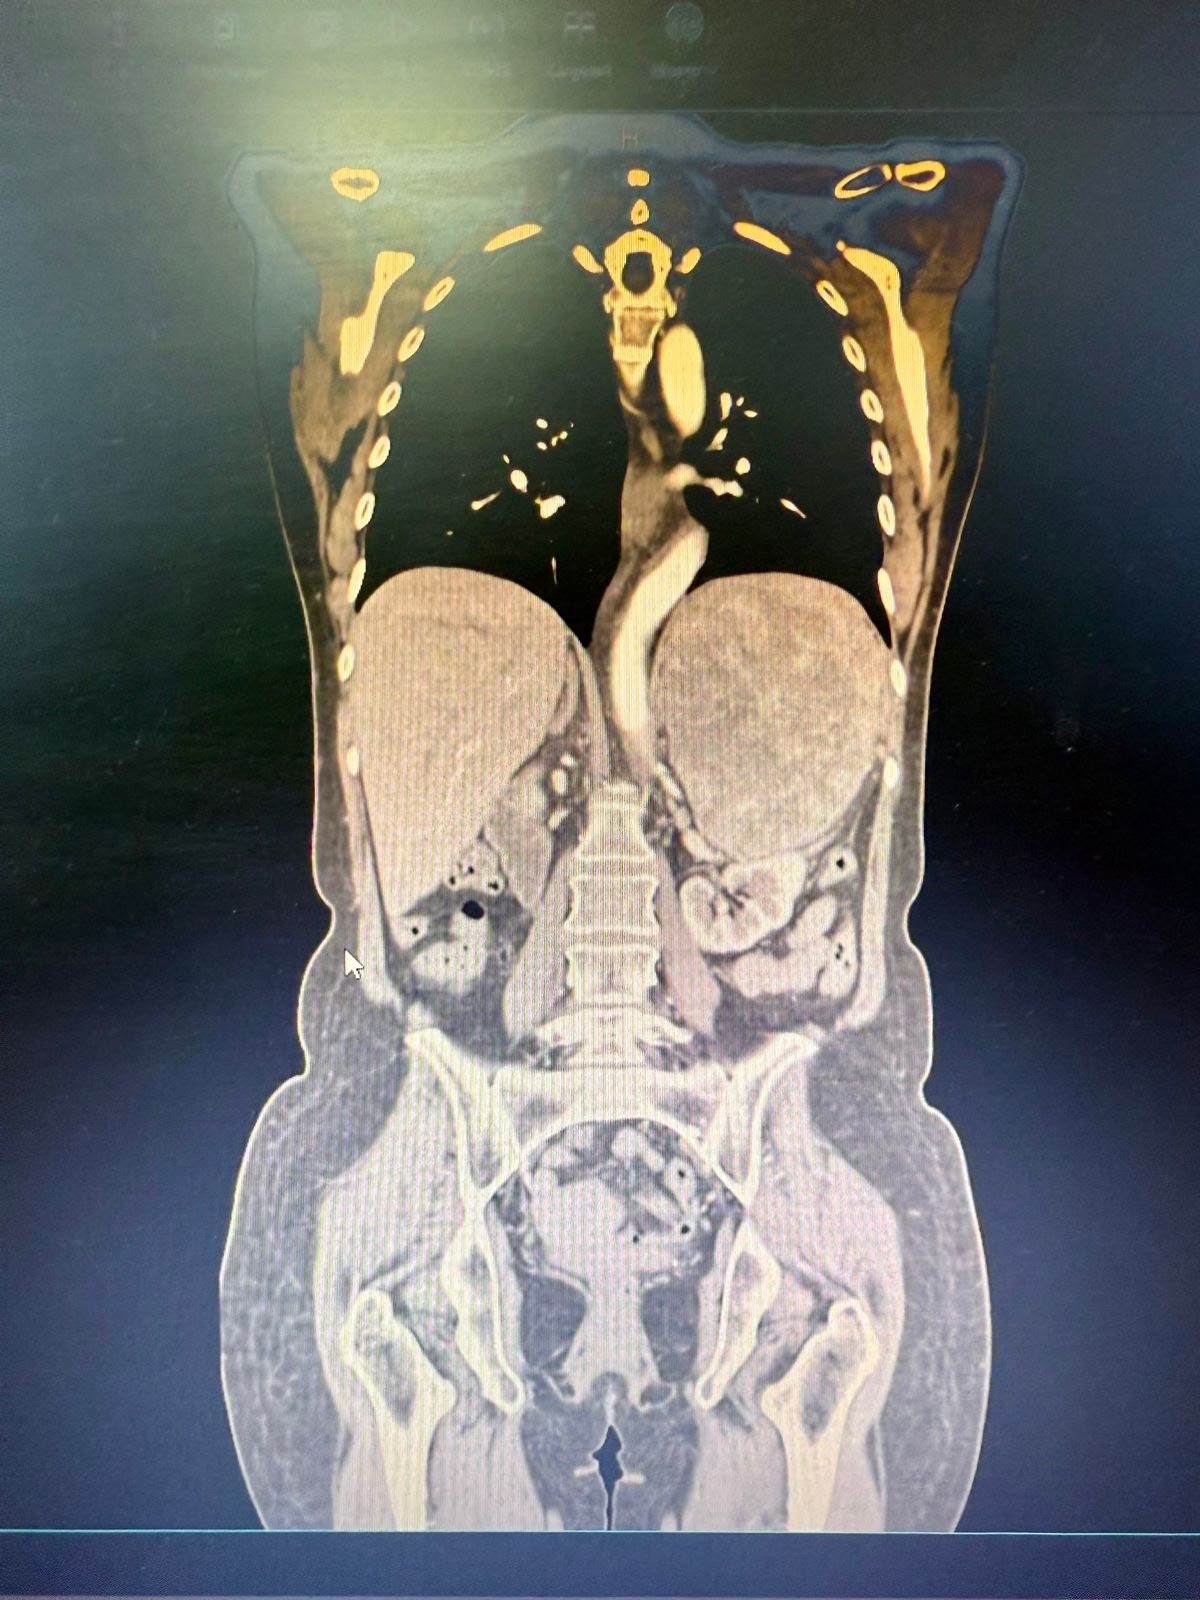

La profesional señala que este caso fue muy desafiante por la alta dificultad que presentó, debido al tamaño del tumor que fue de aprox. 25 cm de diámetro mayor y estaba adherido a otros órganos importantes y a múltiples arterias y venas de diferentes calibres que irrigaban al tumor.

El hallazgo operatorio fue de un tumor suprarrenal izquierdo de aproximadamente 25 cm de diámetro mayor, duro, elástico, de bordes regulares y bien delimitados, hipervascularizado, firmemente adherido al polo renal izquierdo, al parietocolico izquierdo, al hilio esplénico y al hemidiafragma ipsilateral.